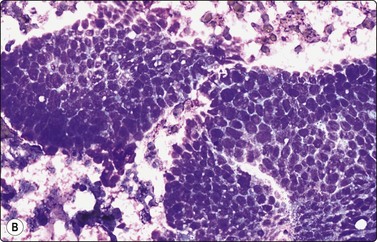

image image

Fig. 14.8 Eccrine spiradenoma

(A) Clustered and dissociated small basaloid cells with relatively uniform dark nuclei; suggestion of acinar/tubular grouping; minimal amount of hyaline stroma (MGG, IP); (B) Corresponding tissue section (H&E, IP).

Spiradenoma is closely related to and resembles cylindroma. Smears are highly cellular, of clustered, variably cohesive small basaloid epithelial cells with uniform oval dark nuclei and a homogeneous chromatin. A more or less obvious acinar/tubular arrangement of the cells is discernible, but a dual population of small dark and larger pale epithelial cells as seen in histological sections is difficult to appreciate in smears. Globules of hyaline stromal material are characteristic but were scant in the case illustrated here (Fig. 14.8). The main differential diagnosis is adenoid cystic carcinoma.29